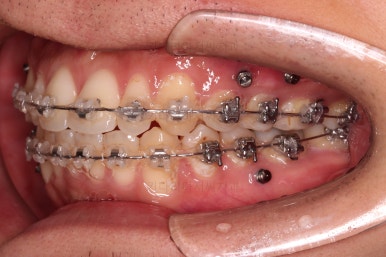

미니스크류도 일반적인 위치가 아니라 전반적인 치열의 높낮이를 조절하기에 용이한 위치에 갯수도 매우 많이 식립하게 됩니다.

한참을 셋팅한 방향으로 치열을 당겨줍니다.

중간평가를 자주 하게 됩니다.

교합이나 가지런한 느낌 매우 좋아졌고요.

특히 옆 라인에서도 둥글었던 윗입술도 오목한 곡선이 생기면서 돌출감이 좋아졌고 턱끝의 윤곽도 생기면서 무턱 느낌도 좋아졌습니다.

윗니의 위치를 보면 처음은 아랫입술에 가려질 정도로 아래로 내려와 있었는데 치료 후에는 앞니가 보이는 정도로 위치 조절이 잘 되었네요.